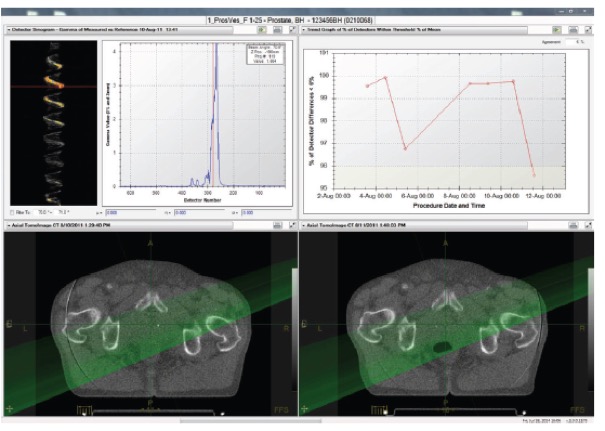

II. Αυτόματη παρακολούθηση της χορηγούμενης ακτινοθεραπευτικής αγωγής

Το σύστημα περιλαμβάνει εργαλεία που επιτρέπουν στον ακτινοθεραπευτή ιατρό να παρακολουθεί την εκτέλεση της ακτινοθεραπείας και να ενημερώνεται αυτόματα για τις περιπτώσεις εκείνες που απαιτείται αναπροσαρμογή του πλάνου θεραπείας.

- Σύντηξη των παραμέτρων του πλάνου θεραπείας (π.χ., περιγράμματα στόχου και κρίσιμων οργάνων) με τις καθημερινές εικόνες αξονικής τομογραφίας λαμβάνοντας υπόψη τις ανατομικές και βιολογικές μεταβολές του ασθενούς

- Υπολογισμός της καθημερινά χορηγούμενης κατανομής δόσης

- Υπολογισμός της αθροιστικά χορηγούμενης δόσης

- Ενημέρωση της ηλεκτρονικής καρτέλας του ασθενούς για την δοσιμετρική ακρίβεια της χορηγούμενης ακτινοθεραπείας

- Ενημέρωση του ακτινοθεραπευτή ιατρού στην περίπτωση που ο όγκος στόχος ή τα κρίσιμα όργανα λαμβάνουν δόση εκτός των κριτηρίων ανοχής που έχει θεσπίσει.

III. Αξιολόγηση ακτινοθεραπευτικής αγωγής

Το σύστημα διαθέτει εργαλεία για την αξιολόγηση των καθημερινά χορηγούμενων κατανομών δόσης επιτρέποντας στους ιατρούς να αναγνωρίσουν πια πλάνα χρειάζονται αναπροσαρμογή.

- Αξιολόγηση της ευθυγράμμισης του ασθενούς σε θέση θεραπείας.

- Αξιολόγηση των ανατομικών και βιολογικών μεταβολών του ασθενούς κατά τη διάρκεια της ακτινοθεραπευτικής αγωγής

- Αξιολόγηση της καθημερινά χορηγούμενης κατανομής δόσης, της αθροιστικής δόσης μέχρι την συγκεκριμένη συνεδρία καθώς και των δοσιμετρικών διαφορών

- Αξιολόγηση της ανταπόκρισης του ασθενούς στην ακτινοθεραπευτική αγωγή.